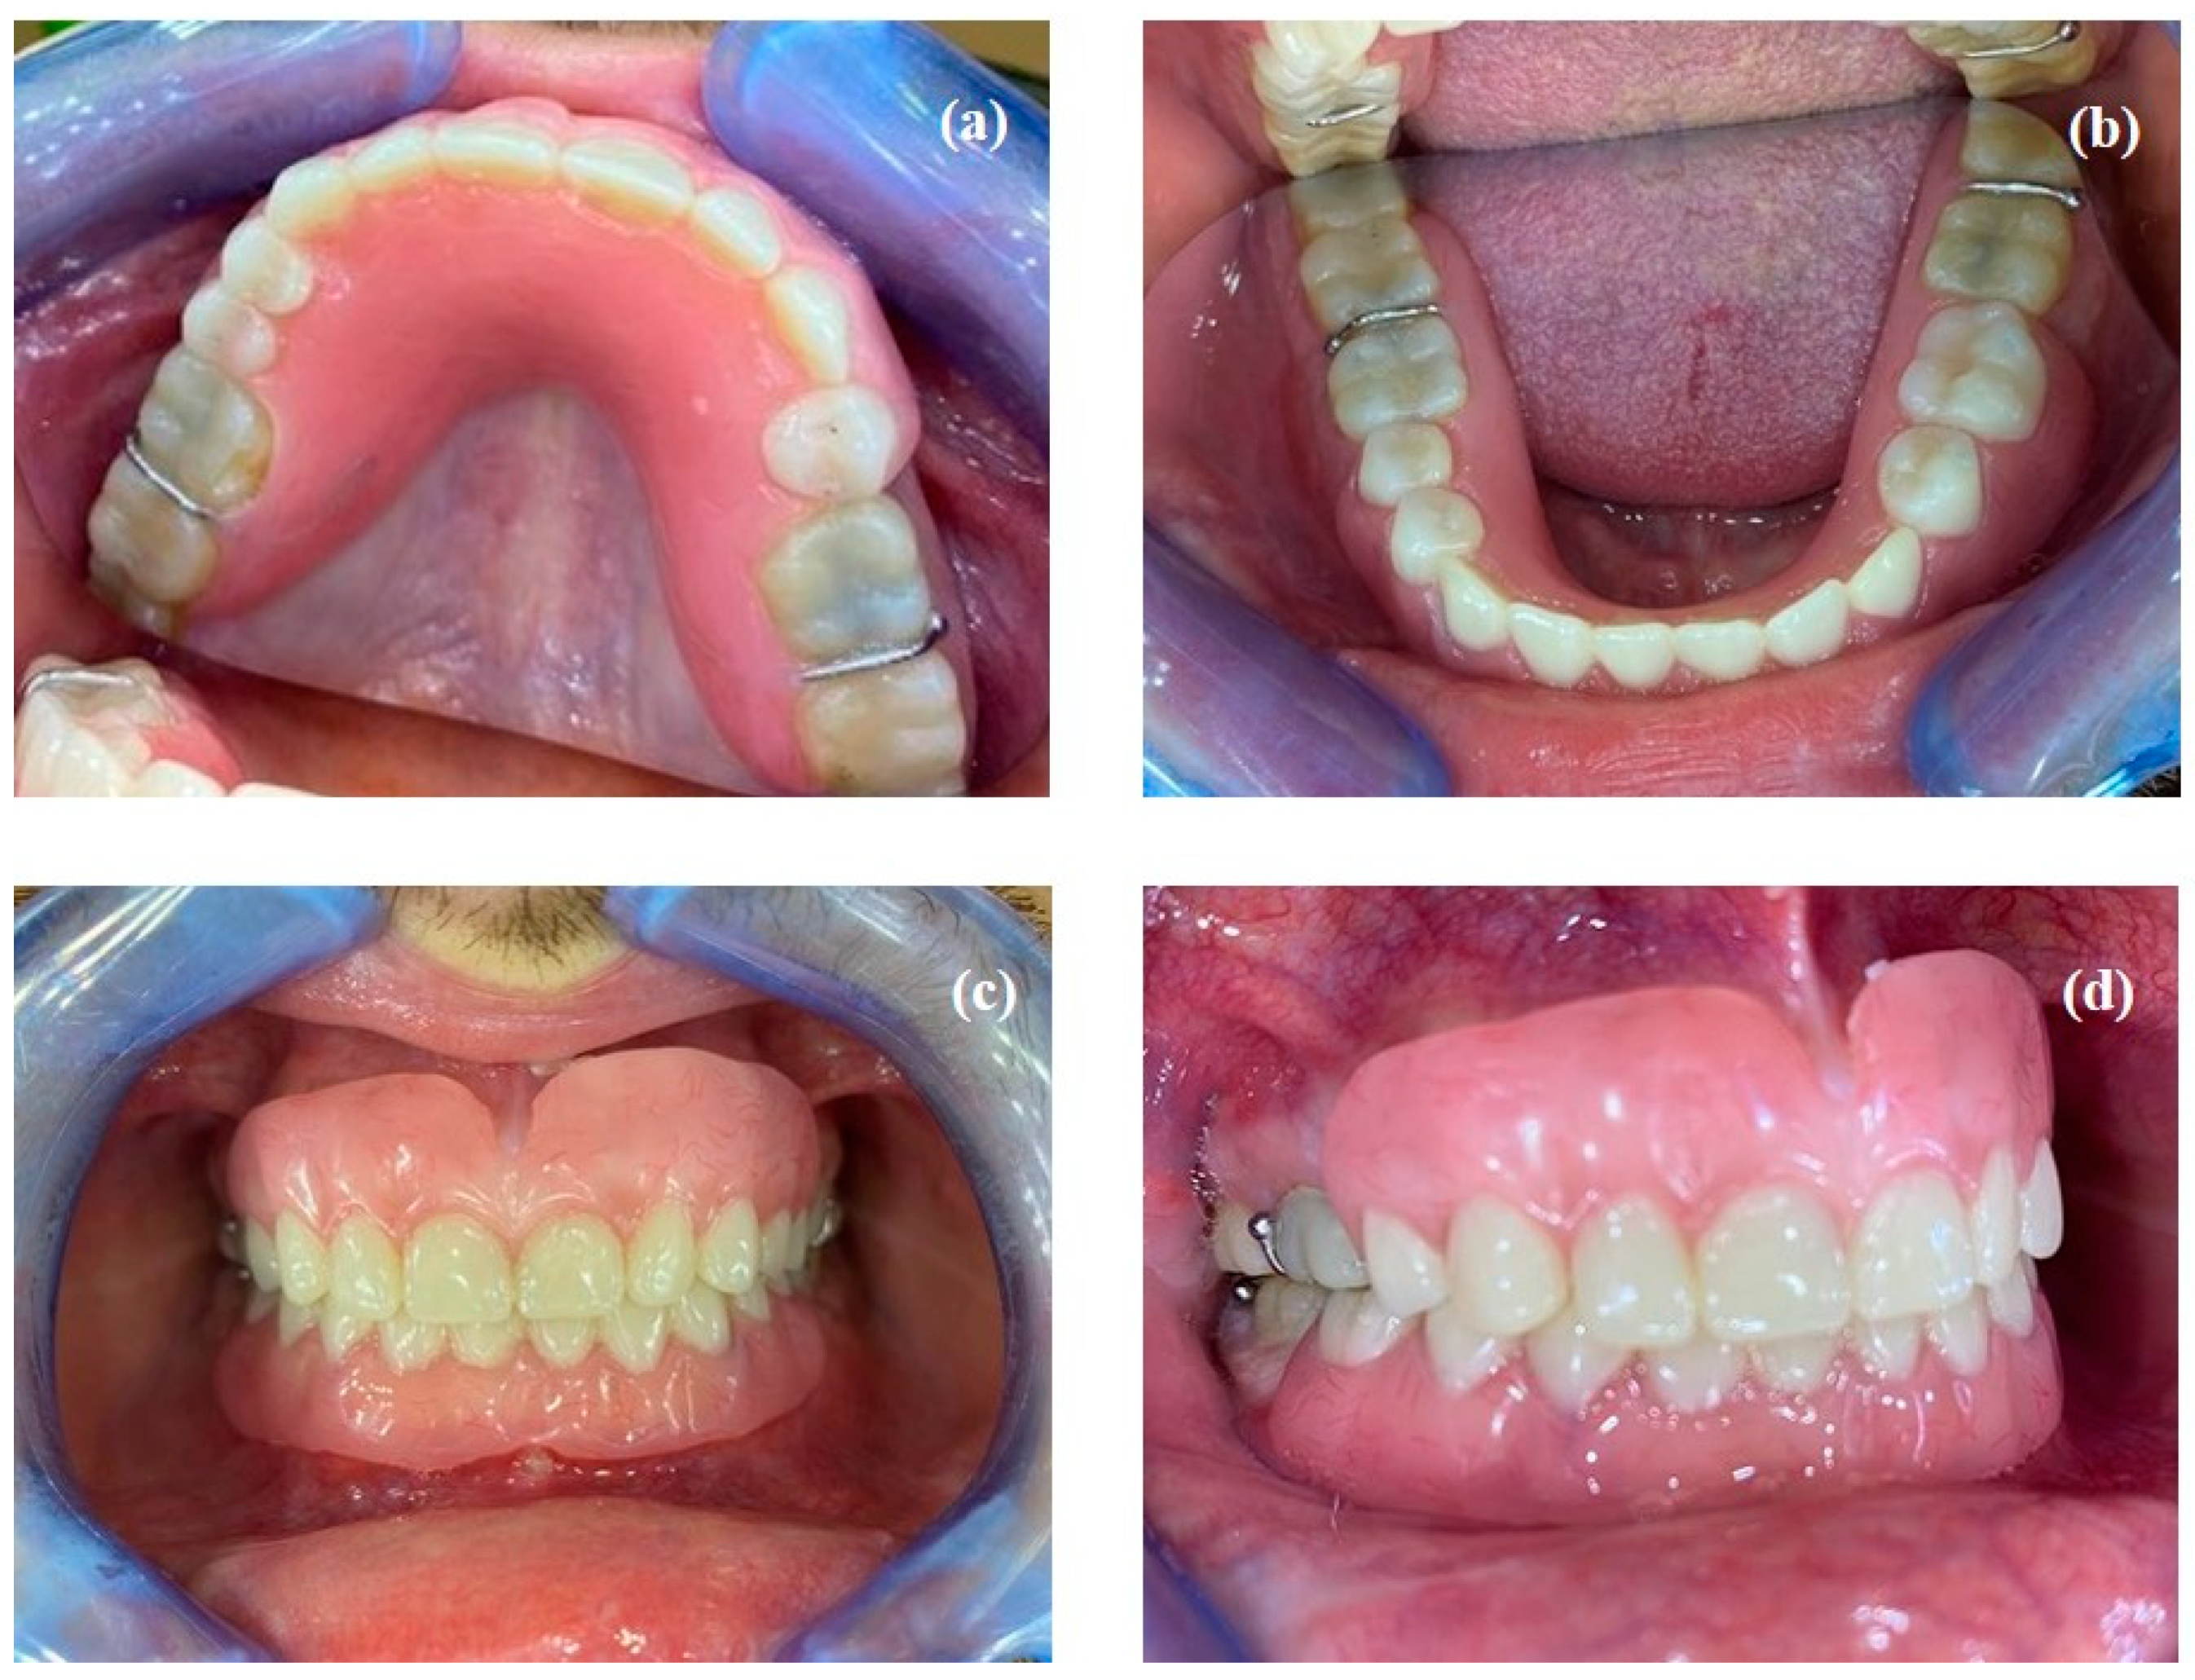

- Fabrication of fixed prostheses: the onlays were fabricated in two clinical sessions using chairside CAD/CAM techniques with a PrimeScan™ intraoral scanner (Dentsply Sirona, York, PA, USA). Two opposing quadrants were restored each session (left posterior segments 2 and 3, then right posterior segments 1 and 4).Preliminary digital impressions with the mock-up in place were made to ensure that the coronal anatomy of the future onlays were identical to the mock-up. The preparation for the onlays consisted of the removal of the mock-up and the occlusal restorations, the curettage of any decay and the preparation of any existing undercuts. Finally, an occlusal reduction was performed to provide sufficient height for the restorative material of the onlays (Figure 8). The onlays were then digitally designed in the same clinical session (Figure 8).The choice of milling material was justified by the very minimal restoration thickness (due to the small occlusal vertical dimension increase). All onlays were therefore milled from hybrid resin/ceramic blocks (VITA Enamic®, Bad Säckingen, Germany). The onlays were bonded intraorally using rubber dam isolation and a light-curing adhesive with no adhesion potential (Variolink® Esthetic, Ivoclar, Saint jorioz, France) in accordance with the manufacturer’s instructions for use (Figure 9).

- Fabrication of definitive removable partial dentures: the definitive prostheses were fabricated using the conventional technique from functional impressions. The patient’s new smile is shown in Figure 10.